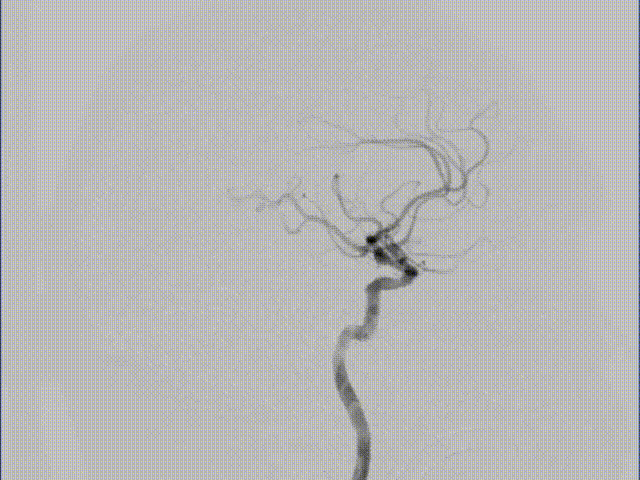

术前DSA:左侧大脑中动脉M1段局限重度狭窄。

6F 90cm 长鞘置于左侧颈内动脉近段,造影显示左侧大脑中动脉M1段重度狭窄,左侧颈内动脉C7段稍膨隆。